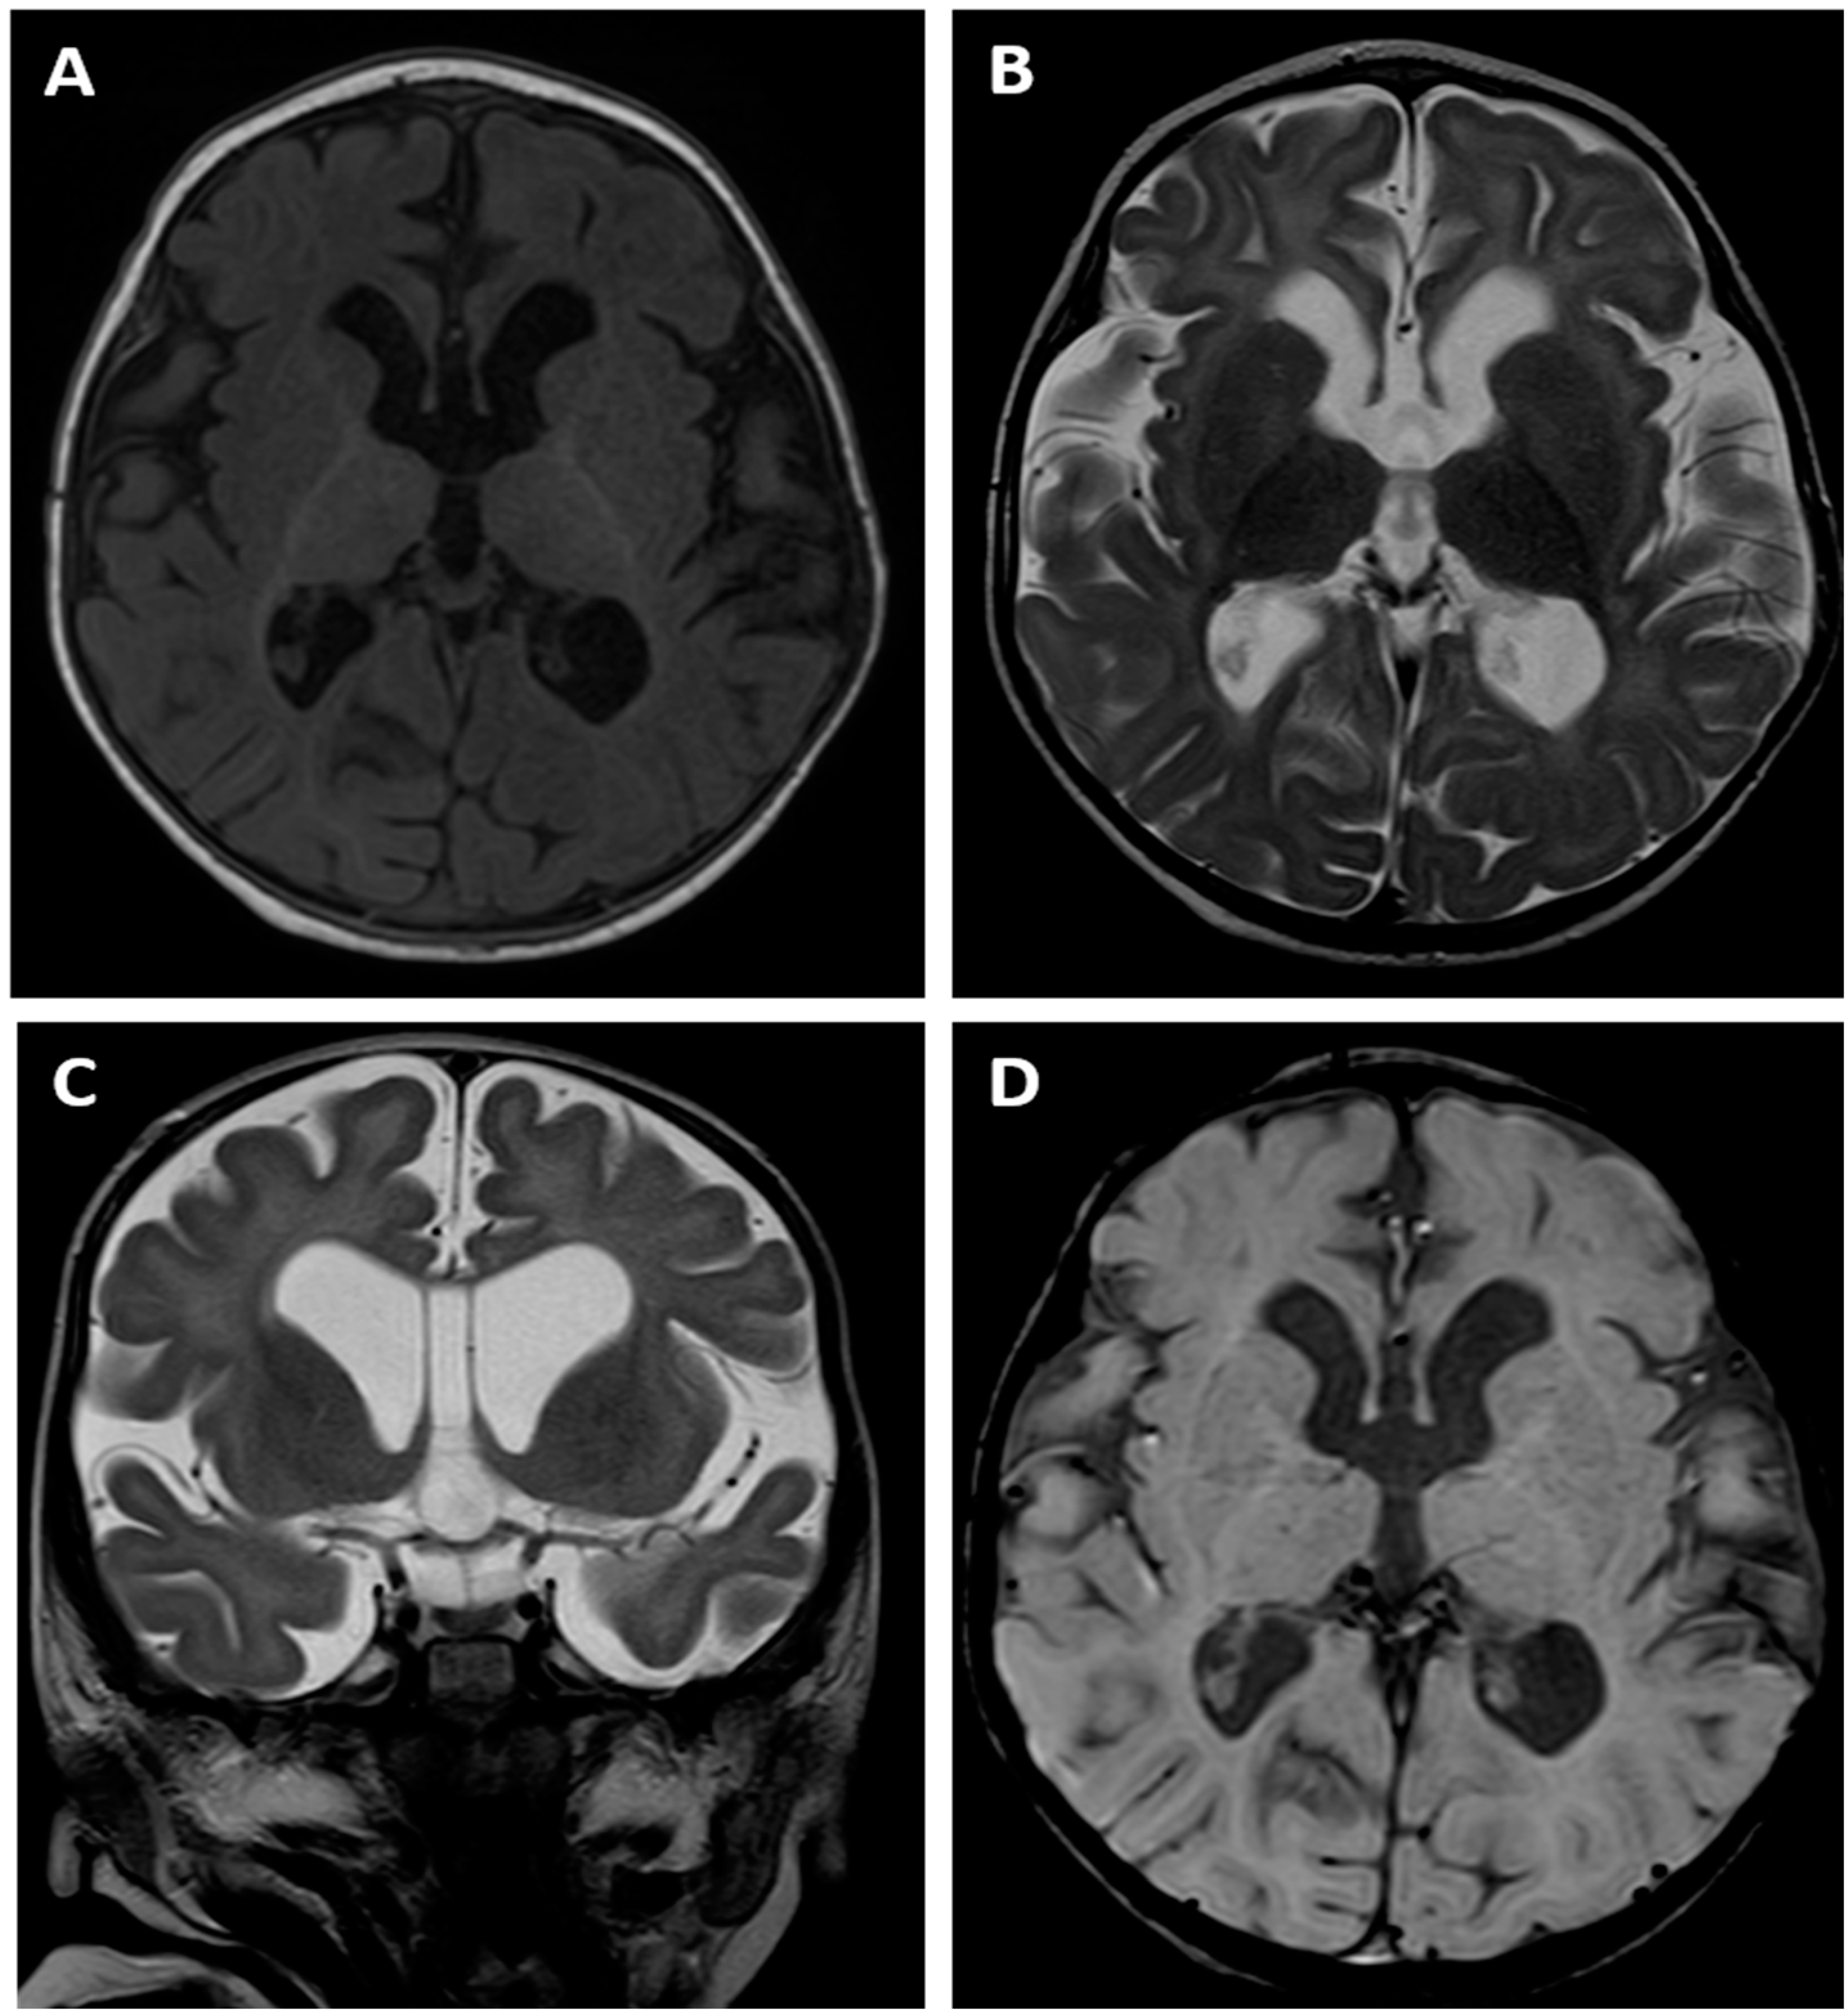

| brain MRI (age at which the test was performed) | cerebral atrophy, delayed myelination (6 and 14 mo) | cerebral atrophy, delayed myelination (14 mo) | cerebral atrophy and delayed myelination (8 years) |